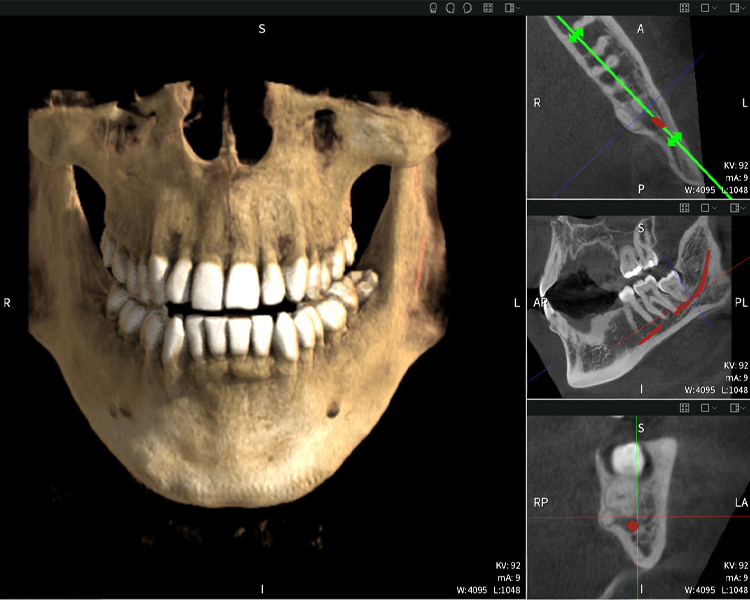

Below you will find a case from Dr. med. dent. Oliver A. Centrella, in which the CBCT images obtained with Seethrough Max provided crucial information on the complex anatomy and the critical relationship between the wisdom teeth and the inferior alveolar nerve. In this case, there is a indication for the surgical removal of the wisdom teeth.

Figure a

- Top left: Axial cross-section of the left mandible (region 38) showing the inferior alveolar nerve (red) in proximity to the roots of tooth 38.

- Top right: 3D reconstruction of the entire mandible for orientation. The red-marked inferior alveolar nerve illustrates its location within the jawbone.

- Bottom left: Sagittal view of the mandible (region 38), highlighting the close spatial relationship between the roots and the nerve canal.

- Bottom right: Coronal view of the mandible (region 38), which is crucial for assessing the spatial position of the roots relative to the nerve.